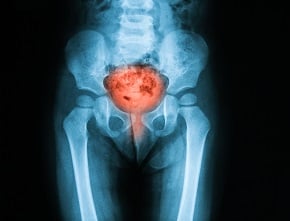

Rak pęcherza moczowego zaliczany jest do jednych z najbardziej niebezpiecznych nowotworów układu moczowego. W Polsce każdego roku umiera na niego około 4 tysiące osób. Charakterystyczne jest, że choroba bardzo często rozwija się w sposób skryty, nie dając wyraźnych symptomów na wczesnym etapie. Mimo to, pierwsze sygnały mogą być zauważalne w bardzo niespodziewanym miejscu – łazience, podczas oddawania moczu.

Najbardziej charakterystycznym i najczęściej pojawiającym się symptomem raka pęcherza jest krwiomocz, czyli obecność krwi w moczu. Może on być widoczny gołym okiem – mocz może zmienić barwę na brunatną, czerwoną lub różową, ale czasem krew jest wykrywana jedynie w badaniu mikroskopowym.